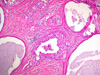

CASO N° 1 (Dr. Jair e Dr. Delgado)

Paciente do gênero masculino, 44 anos de idade, apresenta uma lesão no palato duro e palato mole.